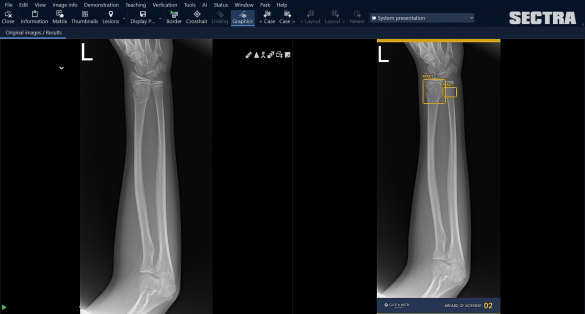

AI applicatie Gleamer Boneview in Sectra PACS AI applicatie Gleamer Boneview in Sectra PACS

Sectra interviewed innovation manager Wilco Kleine and ICT project manager Julia Larsen of Deventer Hospital. The focus of the interview was on their accomplishment in completing the proof-of-concept phase for BoneView, a Gleamer AI program that helps radiologists identify bone fractures. BoneView runs via Sectra Amplifier Services and is integrated into the Sectra PACS. To ensure the success, the pilot project was divided into the following phases: market analysis, retrospective study for local validation, integration testing in shadow mode, and application in clinical practice.

Deventer Hospital will be using AI for various purposes, including reducing workload and improving patient outcomes. In addition, the logistical use of AI will support less complex assessments of an acute nature, the goal being to optimize emergency care, better distribute the workload and improve waiting times for patients. For instance, the BoneView application will allow automation of the initial detection of bone fractures.

During the technical test, the AI application ran in the background for a week without radiologists being able to see and therefore act on the results. The technical test examined a variety of questions: Are all images processed? Do all results come back within the intended time limit? Is the speed not only high on average, but also without very slow exceptions? And are there any adverse effects on the rest of the system? Kleine: “It’s not just about the total package of stability, speed, and performance of the AI application, but also the PACS around it.”